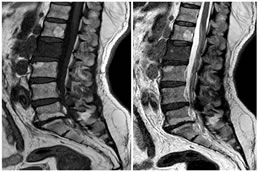

CASE 4

T1 W PARASAGITTAL IMAGE SHOWING OBLITERATION OF THE FORAMINAL FAT PAD WITH EXITING NERVE ROOT COMPRESSION AT L4-L5 LEVEL ON RIGHT CAUSING SEVERE NEURAL FORAMINAL STENOSIS

T1W AXIAL IMAGE SHOWING SEVERE THECAL SAC STENOSIS DUE TO DISC PROTRUSION, CENTRAL EXTRUSION, LIGAMENTUM FALVUM HYPERTROPHY AND FACETAL ARTHROPATHY

T2W MID SAGITTAL IMAGE SHOWING DISC PROTRUSIONS AT MULTIPLE LEVELS CAUSING COMPRESSION OVER THE ANTERIOR THECAL SAC AND ITS CONTAINED NERVE ROOTS